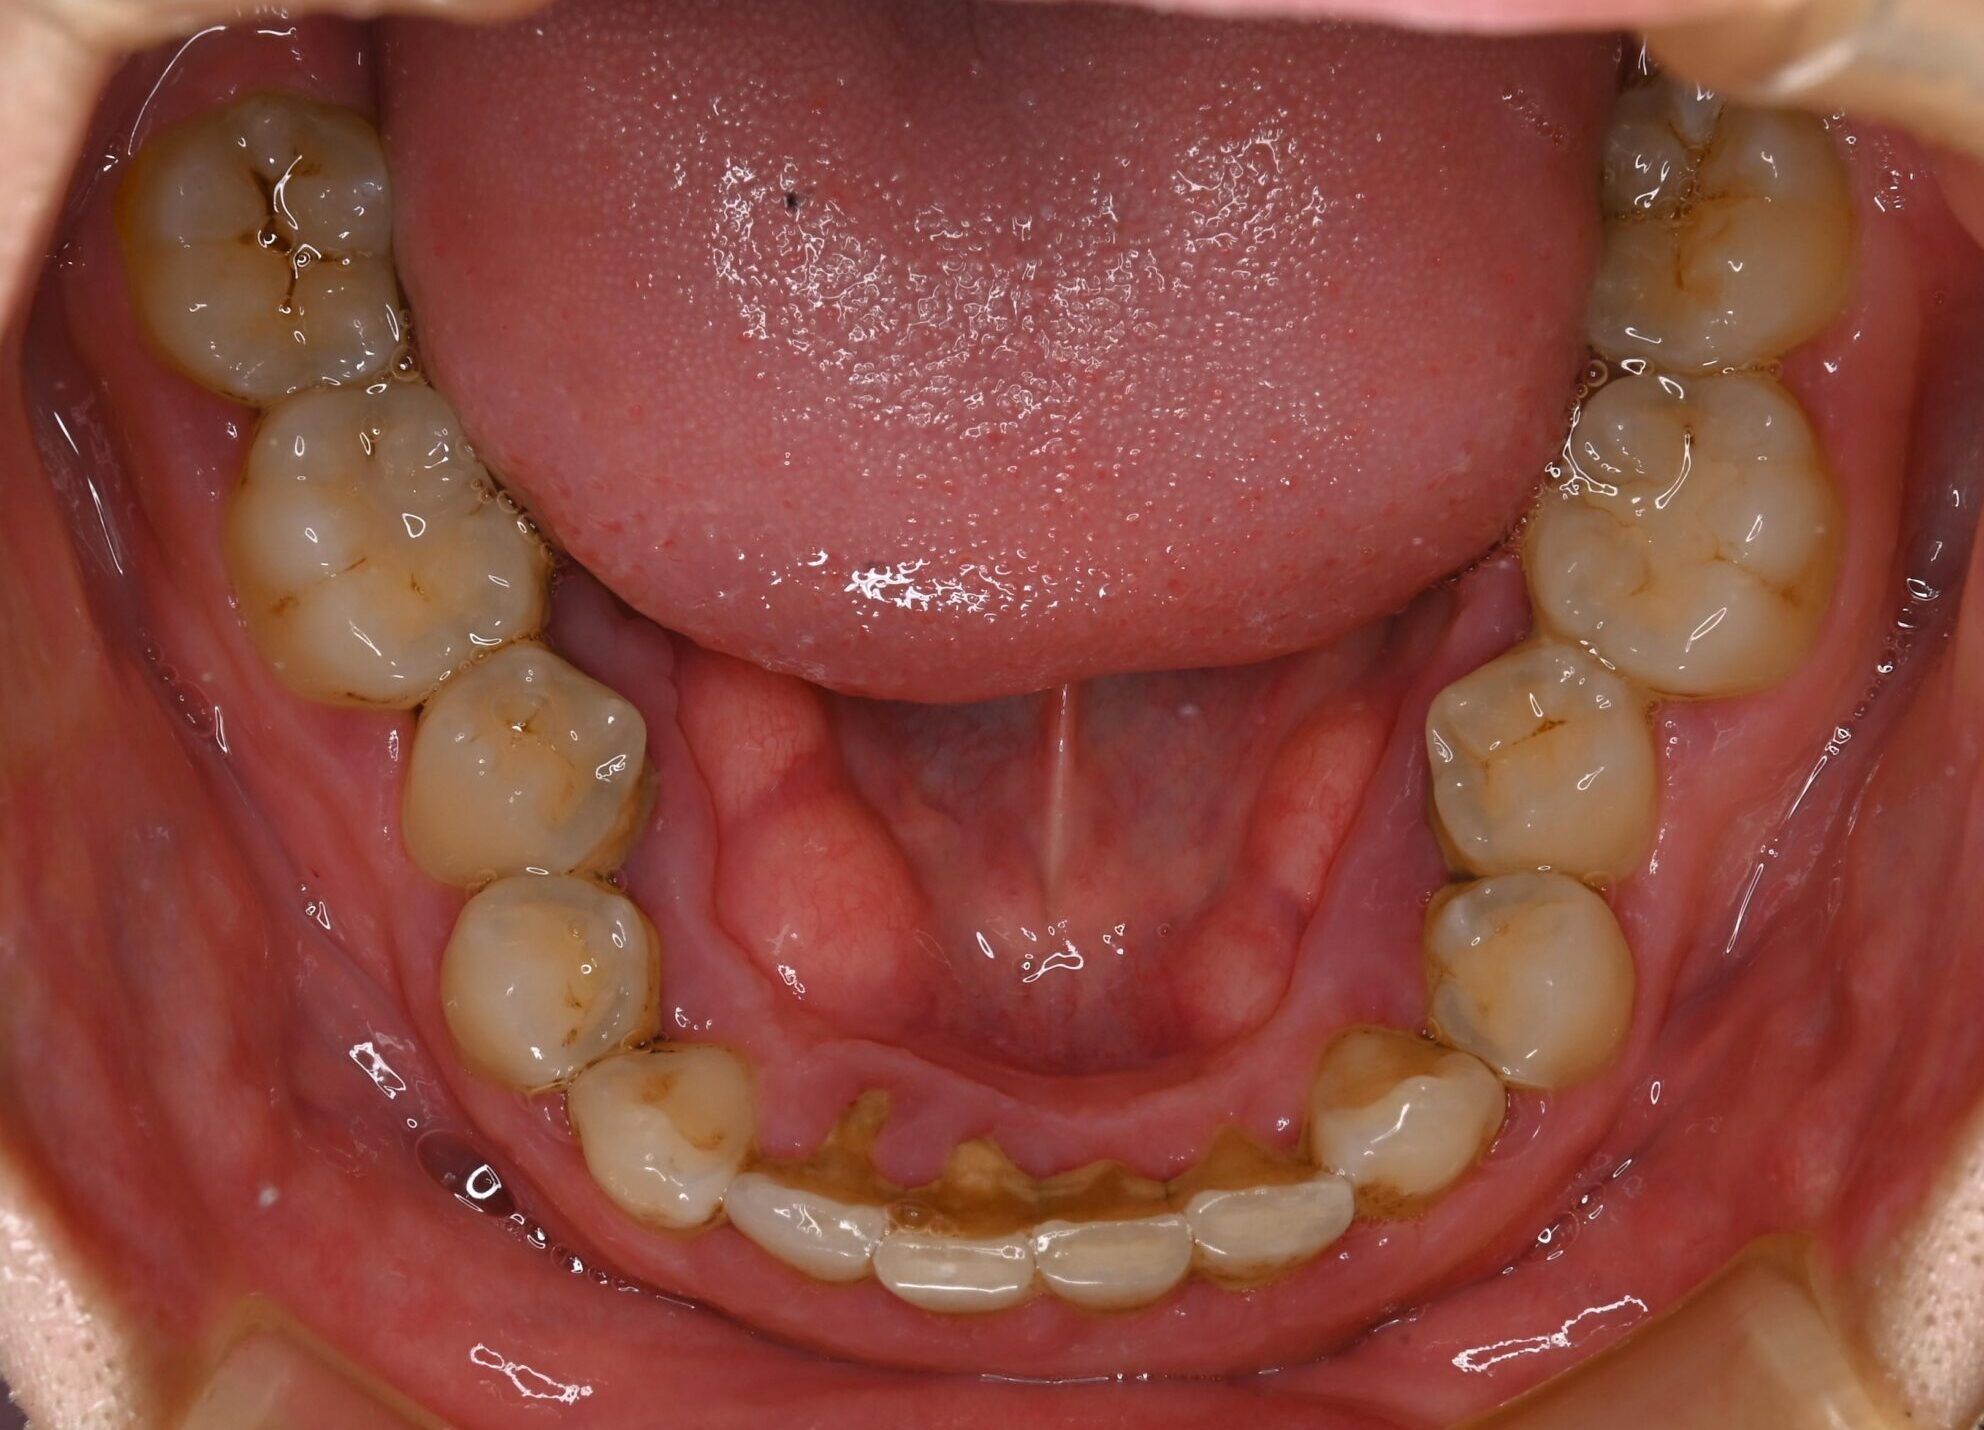

症例写真 before